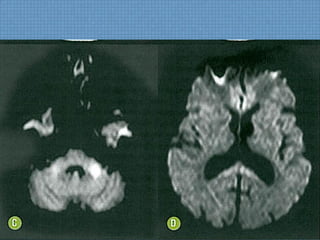

ACHADOS DE IMAGEM

• TC:

– Focos hipoatenuantes subcorticais com alguma

extensão ao córtex adjacente parietocciptal;

– Pode haver contraste puntiforme ao meio de

contraste;

– Podem coexistir hemorragias petequiais na transição

SB-SC;

CASO DO SERVIÇO...

• RM:  Determina diagnóstico e estima prognóstico;

– T1:Hipossinal em topografia subcortical parietoccipal, com

rara impregnação puntiforme pelo Gd;

– T2/FLAIR: Hiperssinal digitiforme parietocciptal, podendo

estender-se para as regiões cerebrais anteriores, além do

NB;

– SWI: Permite diagnóstico de hemorragia de permeio 

Hipossinal;

DIFUSÃO!

Usualmente normal  Só edema vasogênico;

Se restrição  Dano cerebral irreversível;

ECLÂMPSIA